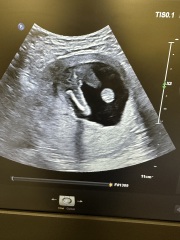

Any guess ?

Girl or boy